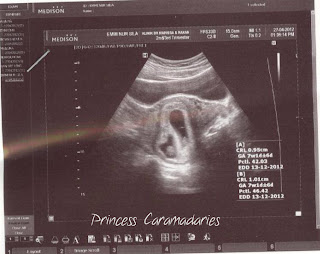

Saya dah pregnant 8 minggu

Hari ini saya wat appoinment utk scan baby

ada dua degupan jantung kedengaran...

Baby sihat

Saya risau, Doc ckp ada cyst

cyst cuma lah ketulan lemak sahaja

emme! rs nk menangis tgk 2 sac dlm gambar tu! congrats emme! semoga berjaya membawa kedua baby mu ke dunia. sy mendoakan yg terbaik utk awk emme.